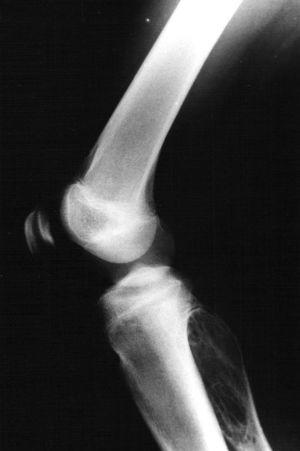

Fig. 3.--Radiografía lateral de la rodilla derecha. Gran lesión lítica expansiva en la metáfisis proximal del peroné derecho sin halo esclerótico, con septos internos, sin matriz ósea y limitada superiormente por la placa de crecimiento.

Paciente varón de 15 años, que fue remitido a consultas de traumatología por genu valgo. No tenía antecedentes de interés, salvo crisis asmáticas en la infancia, y la presencia de una lesión lítica ya conocida en el peroné, que sugería el diagnóstico diferencial de displasia fibrosa o quiste óseo aneurismático como primeras posibilidades. La lesión parecía haber crecido respecto a estudios previos. En la radiografía simple (fig. 3), se identificaba una gran lesión lítica expansiva que afectaba predominantemente a la metáfisis proximal del peroné derecho, extendiéndose caudalmente a la diáfisis, y limitada superiormente por la placa de crecimiento. No tenía matriz ósea interna y la zona de transición, al menos en la zona inferior, era estrecha. En el interior presentaba un patrón de múltiples septos con cierto adelgazamiento endostal. En la TC (fig. 4) la cortical estaba muy adelgazada, con focos de discontinuidad sin identificar masa de partes blandas, y presentaba finos septos internos. Se realizó un estudio mediante RM con un equipo de 1,5T (Gyroscan Philips Intera). En la RM el tamaño aproximado de la lesión era de 8,5 x 3,3 x 3 cm (craneocaudal x anteroposterior x lateromedial). La lesión insuflaba el peroné sin visualizar masa de partes blandas. En la secuencia T1-ES (TR/TE 460/15) se comportaba hipointensa de forma homogénea (fig. 5). En la secuencia STIR (1688/15) (fig. 6) parecía tener dos componentes, con diferentes intensidades de señal. El superior hipointenso y el inferior levemente hiperintenso. En la secuencia dinámica T1 (TR/ TE 460/15) tras gadolinio itravenoso (figs. 7 y 8) presentaba un leve realce periférico del componente superior en fase tardía con prácticamente nulo realce en fase precoz y, sin embargo, un intenso realce del componente inferior en fase precoz, seis segundos después de que el contraste se identificase en el interior de los vasos arteriales, con realce persistente en fase tardía (fig. 9). Se realizó una gammagrafía ósea de cuerpo completo en proyecciones anterior y posterior en tres fases. En la fase vascular se observaba un incremento en la llegada del radiotrazador del pool sanguíneo a la región proximal del peroné derecho. La imagen tardía mostraba una hipercaptación en el extremo proximal de dicho hueso. Descartaba la posibilidad de quiste óseo, que no suelen mostrar captación en la gammagrafía y aconsejaban descartar otro tipo de tumoración ósea. No se visualizaron otras lesiones a distancia. En estos momentos el diagnóstico diferencial propuesto fue de fibroma condromixoide, fibroma desmoplásico y quiste óseo aneurismático, a pesar de la ausencia de niveles líquido-líquido. A continuación se realizó una biopsia abierta, con diagnóstico de fibroma desmoplásico. En el estudio macroscópico se identificaban varios fragmentos blanquecinos de consistencia ósea. En el estudio microscópico, se identificó una proliferación de células elongadas, separadas de abundantes fibras de colágeno. La densidad celular era muy variable en función del campo estudiado, lo mismo que la disposición de las fibras de colágeno, bien onduladas o con gran laxitud. Las células tenían núcleos ovoideos, sin aparentes nucleolos y sin figuras mitóticas. Algunos de los remanentes óseos atrapados en la muestra tenían actividad osteoclástica, sin ver en ningún momento atipias.